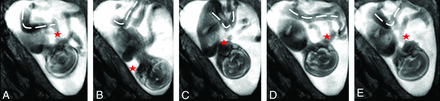

Recent cine MR imaging studies, in which an enlarged FOV allows full coverage of the fetus, confirm that rotations, flexions, and extensions in all the main anatomic regions (upper limbs, lower limbs, head, and trunk) can be observed during intrauterine life. Less frequent were yawns and other mouthing movements including swallowing. Eye and paradoxic breathing movements could also be observed at all ages, as well as kicking, brief twitches, and startles (Fig 4).15

Successive snapshots of a cine bFFE acquisition obtained at 1.5T (TR, 3.21 ms; TE, 1.59 ms; slab thickness, 30–40 mm; scanning duration, 30 seconds for 100 dynamic scans) of a 25-week-old fetus moving inside the uterus. The range and direction of movement of the fetal head (red star) and body and legs (dotted lines) at 6 (A), 12 (B), 18 (C), 24 (D), and 30 (E) seconds can be appreciated.